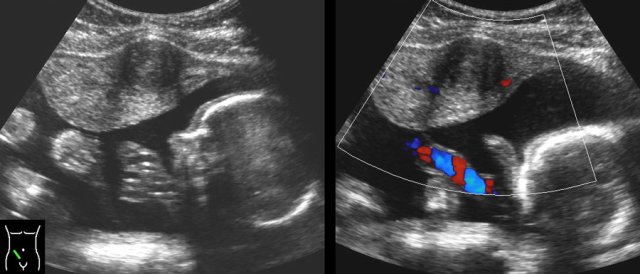

case 2

Young woman with acute pain RLQ and a CRP of 75.

TVUS

shows an irregularly enlarged, inhomogeneous

right ovary with blurred follicles and surrounded by hyperechoic fat (*).

The left ovary is slightly hyperaemic, but otherwise

normal.

There is turbid fluid (f.) in Douglas pouch, representing pus (CRP 75).